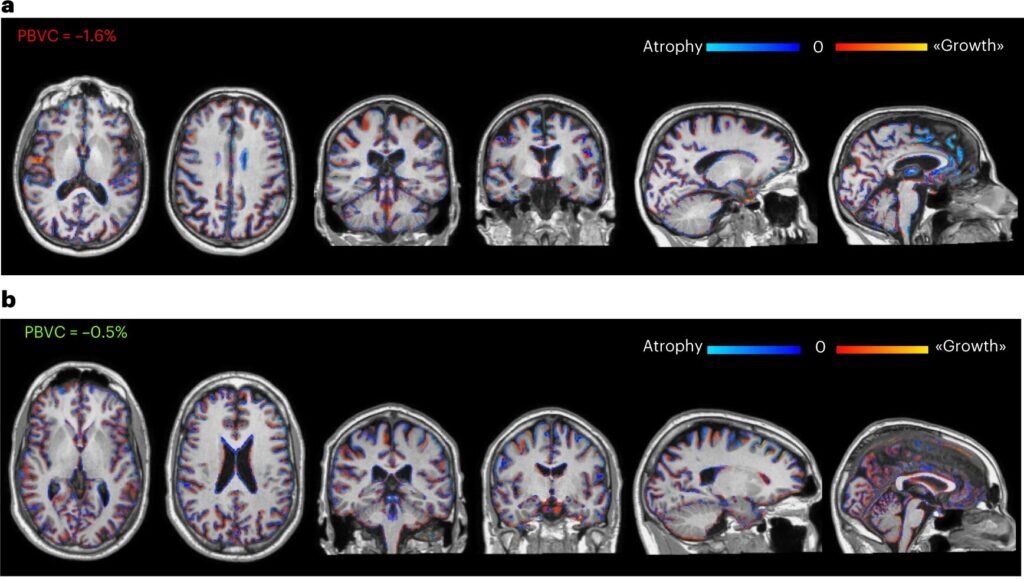

МРТ головного мозга с отмеченными цветными областями атрофии (синий) и роста (красный) серого вещества головного мозга через 2 года после трансплантации нейрональных стволовых клеток-предшественников у двух репрезентативных пациентов, получавших низкую дозу (а) и высокую дозу (б) стволовых клеток / © Genchi A. et al, Nature Medicine, 2023

Через три месяца после процедуры инъекции у пациентов взяли образец спинномозговой жидкости для измерения уровней нейропротекторных и противовоспалительных молекул, маркеров рассеянного склероза. Они оказались выше по сравнению с показателями до начала лечения, а значит, терапия явно пошла пациентам на пользу. Также, судя по результатам МРТ, положительный эффект наблюдался и спустя почти два года после трансплантации: люди, которым вводили наибольшую дозу стволовых клеток, меньше всего потеряли серого вещества.